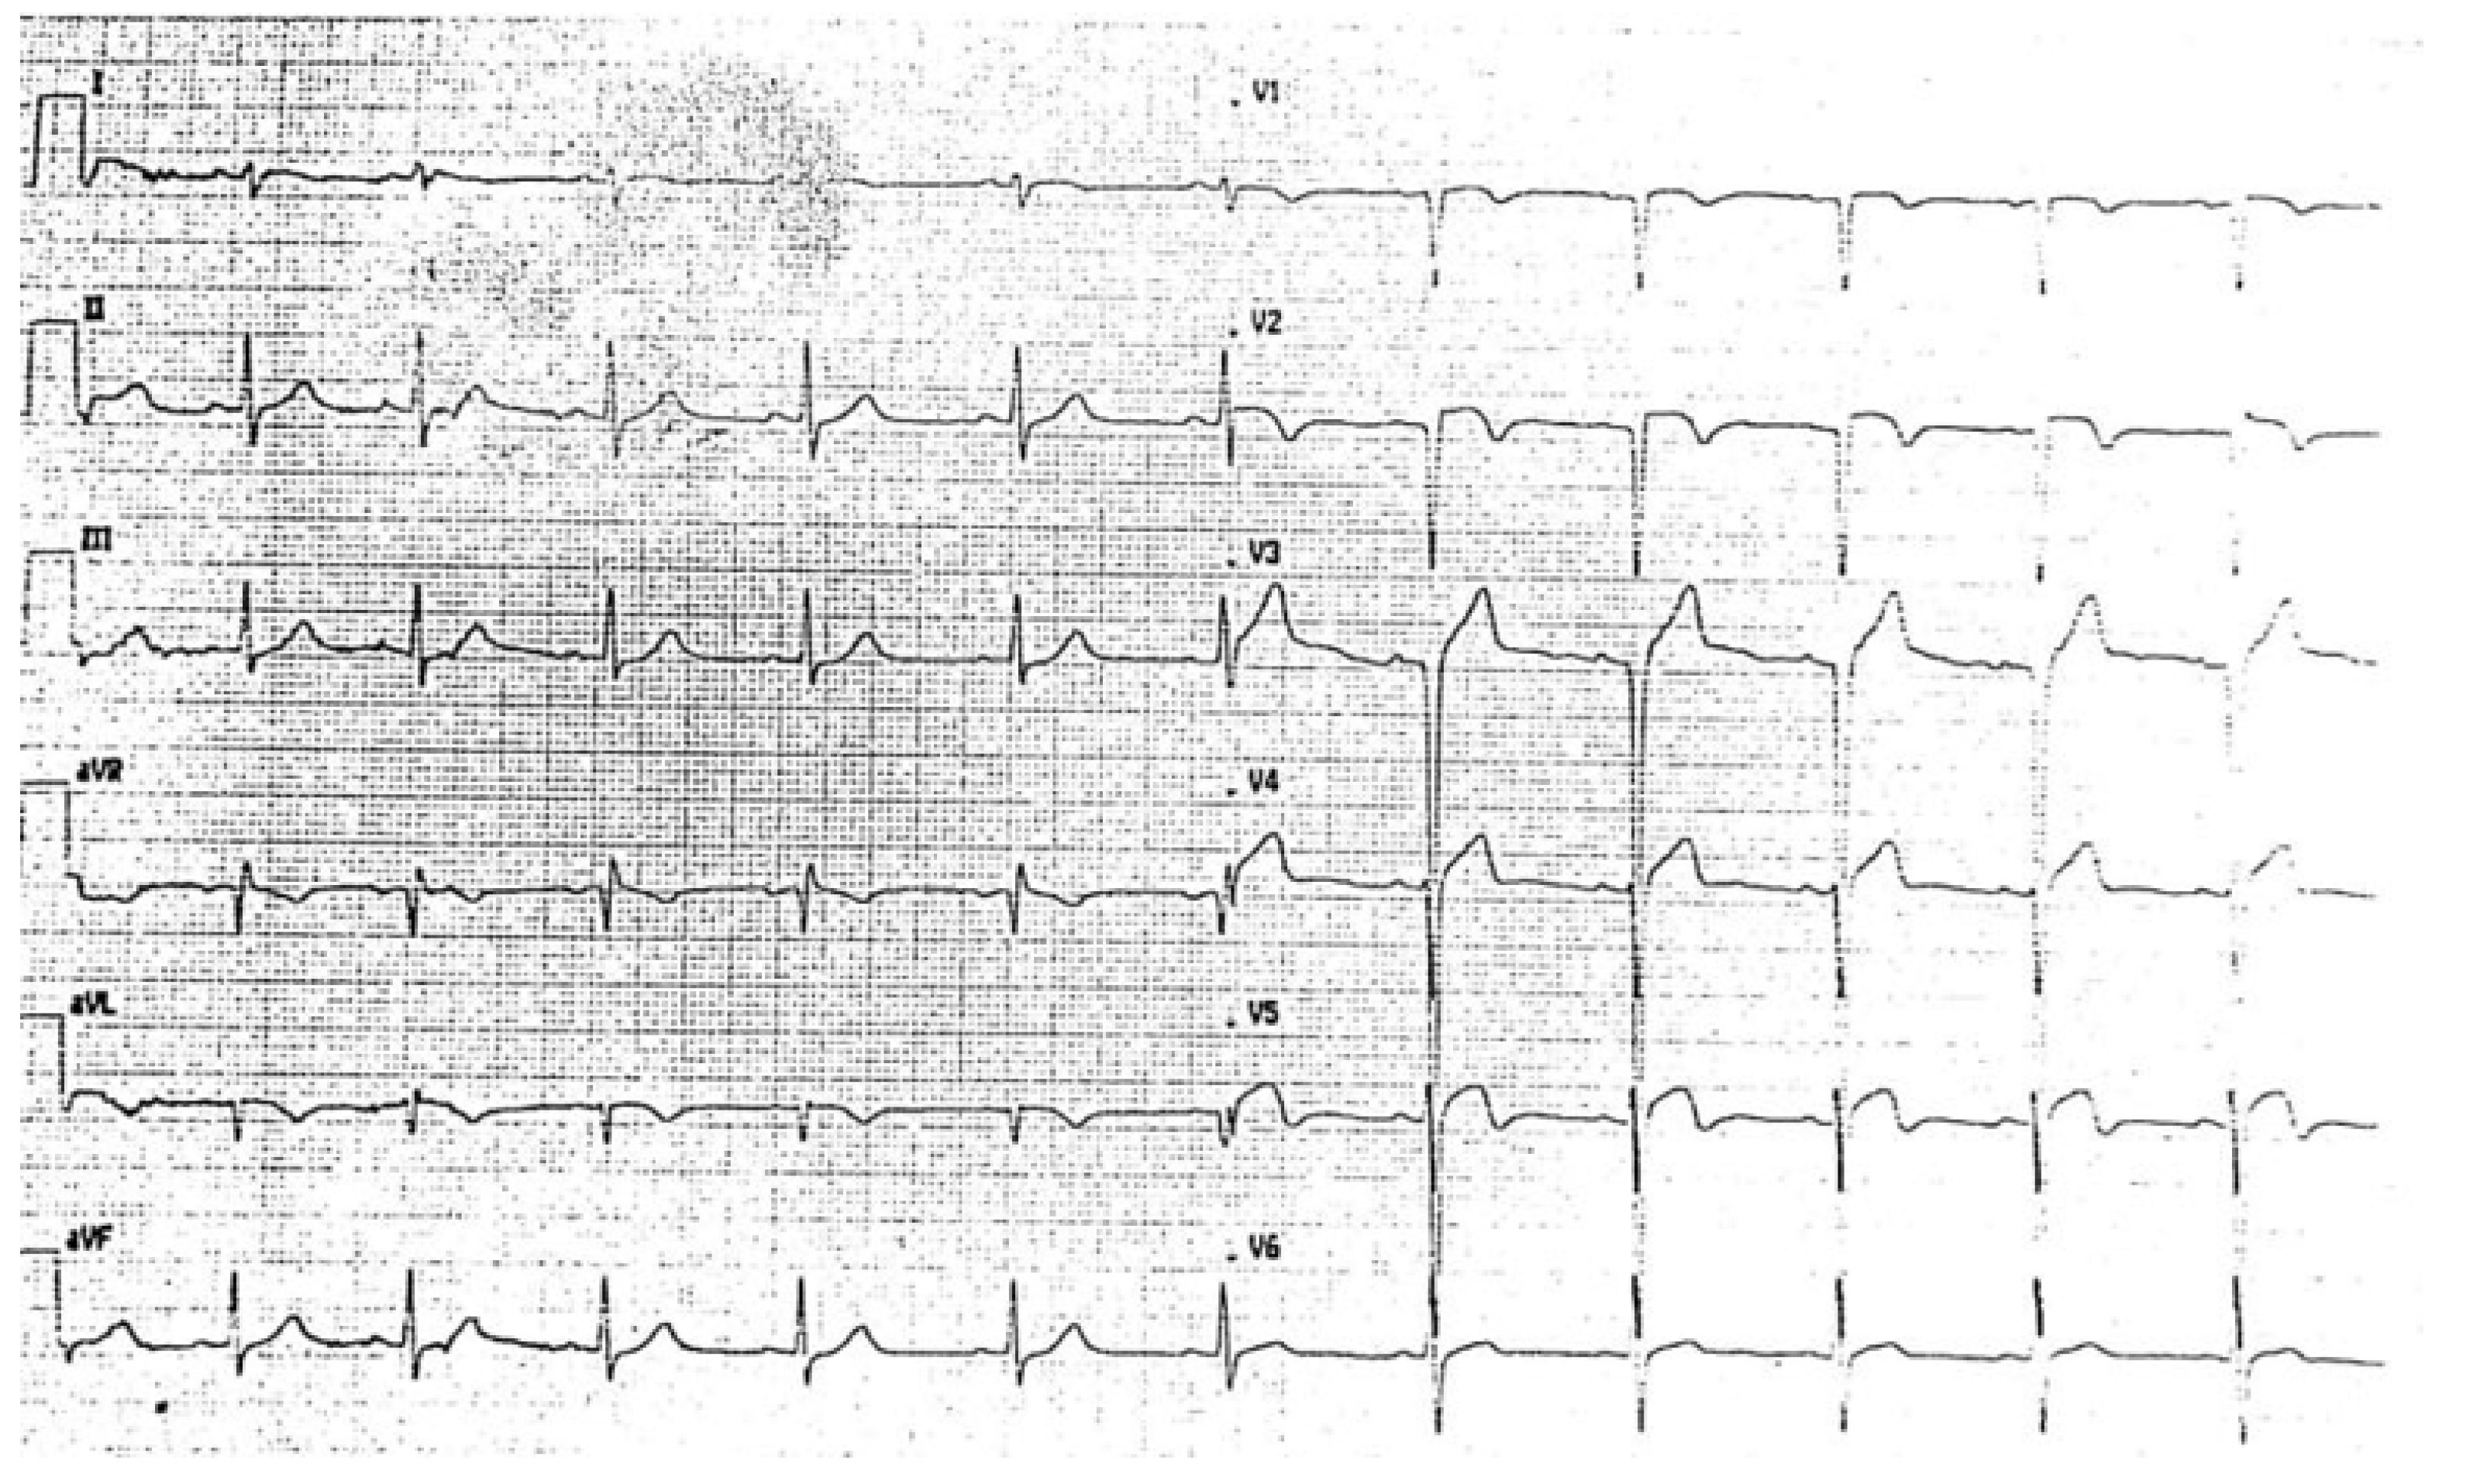

EKG on the 3rd day after reperfusion showed QS complexes in the anterior leads and diffuse ventricular repolarization abnormalities, with preserved atrio-ventricular and intra-ventricular conduction (Figure 3).

Figure 3.

EKG on 3rd day after reperfusion documented QS complexes in the anterior leads and diffuse ventricular repolarization abnormalities, with preserved atrio-ventricular and intra-ventricular conduction.